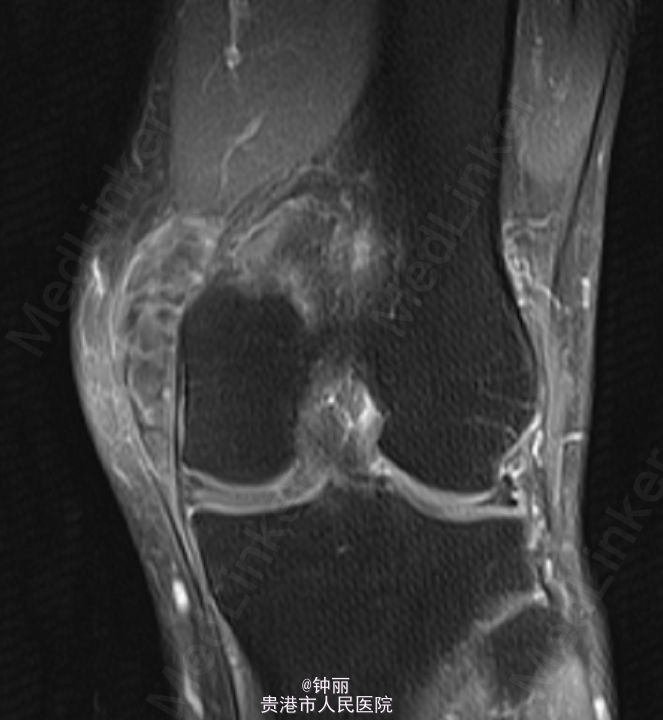

患者左膝内侧可及约8*5cm左右肿块,肿块质韧,无压痛,边界尚清。关节活动无受限,浅表静脉无怒张,末梢足趾下下肢感觉、活动可,余肢体无殊,病理征阴性。左膝关节增强MR:左膝部(股骨下端内侧髁内后方)混杂信号占位,考虑滑膜肉瘤可能,左膝内侧半月板后角撕裂,左膝关节囊少量积液。